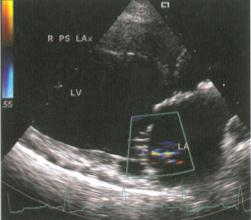

Изобр 2

Слабовыраженная митральная регургитация показана относительно малой зоной турбулентного потока у пуделя с ДКМП. Обратите внимание на дилятацию левого предсердия и левого желудочка.

Правая парастернальная позиция по длинной оси левого желудочка. LA , левое предсердие; LV, левый желудочек.